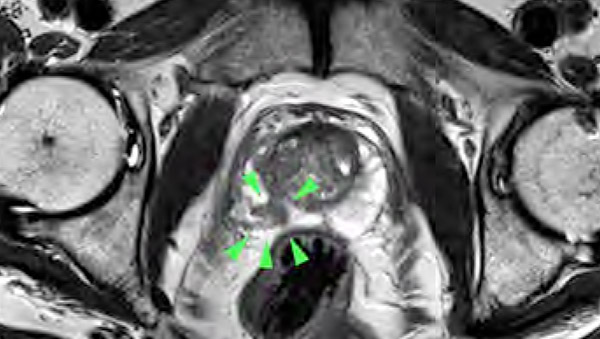

Dr. Dick: Die bisherige Diagnostik weist Lücken auf: So kann der PSA-Wert auch bei nicht-bösartigen Prostata-Vergrößerungen erhöht sein. Und die Abtastung der Prostata ist weder angenehm noch genau. Beim transrektalen Ultraschall über den Mastdarm werden Tumore häufig nicht erfasst und auch die sonographisch gesteuerte Biopsie weist diagnostische Schwächen auf. Deshalb hat die urologische Gesellschaft die multiparametrische Magnetresonanztomografie (mpMRT) in die Leitlinie mit aufgenommen. Diese MRT-Methode ist genau und schonender für den Patienten, auch muss ihm bei 3 Tesla- Geräten keine Spule mehr in den Enddarm eingeführt werden. Neben der Messung anatomischer Werte werden bei diesem speziellen MRT auch die Zelldichte gemessen und die Gewebedurchblutung nach der Gabe von Kontrastmitteln durchgeführt, wodurch wir eine sehr gute Diagnostik haben. Die Datensätze können dann mit den Ergebnissen der Ultraschalluntersuchung verglichen werden. Anschließend kann - wenn nötig - eine gezielte Gewebeprobe entnommen werden.

Mit dem Hochfeld MRT mit 3 Tesla von Siemens steht der Radiologie Darmstadt die neueste Technik – ein hochmodernes Gerät für die mpMRT zur Verfügung - nicht-invasiv und treffsicherer als die ungesteuerte Biopsie. Durch die Kombination räumlich hochauflösender Bilder mit Zelldichtemessungen können wir selbst kleinste Tumore unter 1 cm zuverlässig detektieren. Außerdem können wir entscheiden, ob es sich um einen gutoder bösartigen Tumor oder um eine Entzündung handelt. Die Datensätze können dann mit den Ergebnissen der Ultraschalluntersuchung verglichen und gezielt die richtige weitere Vorgehensweise geplant werden. Neben dem hochmodernen MRT-Gerät verfügen wir als einziger Standort in Südhessen über eine spezielle Software zur Auswertung nach neuesten Richtlinien. Die Auswertung der Daten stellt besondere Anforderungen an den Befunder. Als Praxis sind wir über den BDR (Bund Deutscher Radiologen) zertifiziert, und persönlich bin ich von der Arbeitsgemeinschaft Uroradiologie der Deutschen Röntgengesellschaft mit der Qualitätsstufe Q1 für die mpMRT zertifiziert.